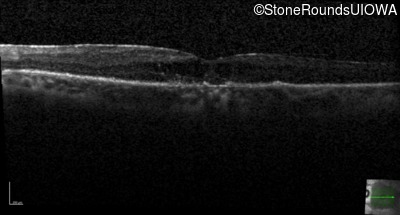

Age at visit: 67 years

Age at visit: 68 years